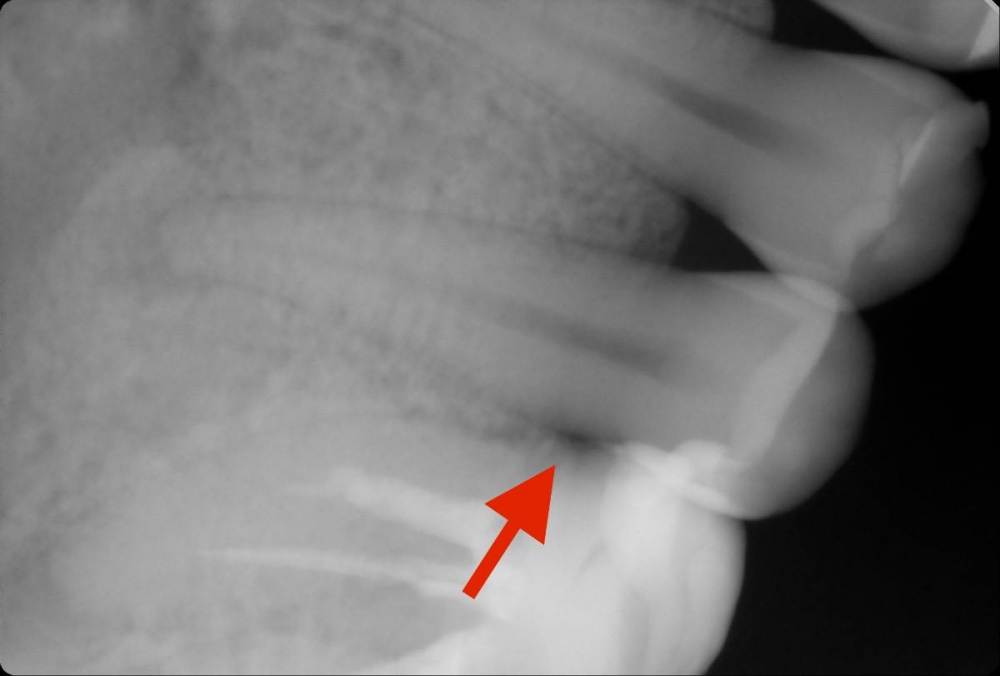

chacraborti Опубликовано 12 марта, 2023 Поделиться Опубликовано 12 марта, 2023 Поскажите, есть ли кариес на левой пятерке снизу? Темное пятно ниже пломбы. Ссылка на комментарий

Carioznik Опубликовано 12 марта, 2023 Поделиться Опубликовано 12 марта, 2023 Это не кариес 1 Ссылка на комментарий

chacraborti Опубликовано 13 марта, 2023 Автор Поделиться Опубликовано 13 марта, 2023 @red_butler Зуб реагирует на холодное, горячее, кислое, сладкое, боль кратковременная, проходит через секунду. Зуб витальный (делали холодовую пробу). Ссылка на комментарий